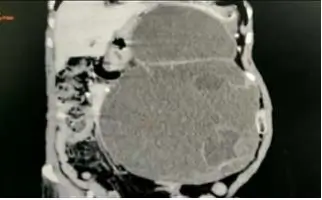

CECT abdomen with proper protocol performed, suggestive of large cystic mass of about 33x25 cm size which was extending from left dome of diaphragm to pelvis compressing all near-by structures and identified to be arising from distal body of pancreas probably mucinous cystadenoma of pancreas.